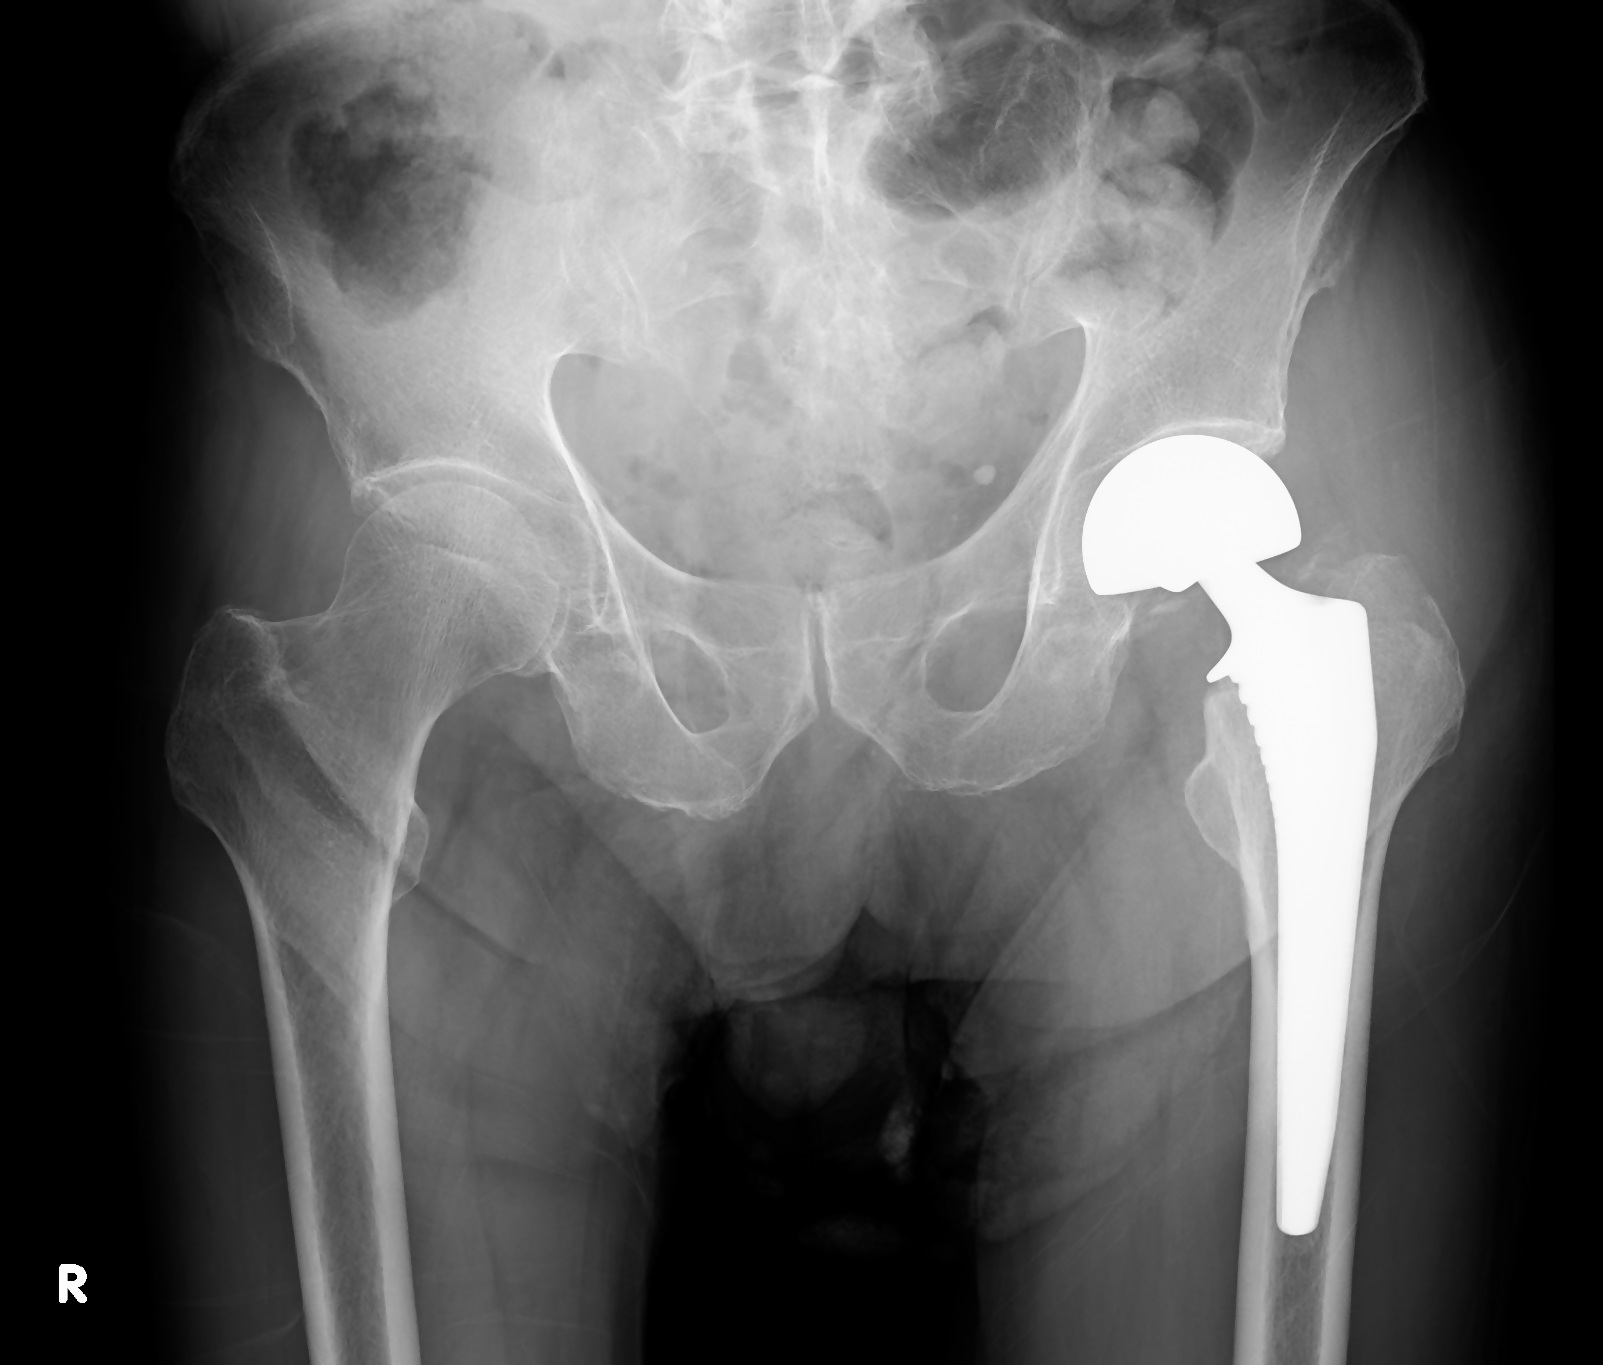

レントゲン写真 - 人工骨頭置換術(BHA)

骨折部のずれが大きい場合や、骨癒合が期待しにくい高齢者に主に実施されます。骨折した頸部から骨頭までを切除し、金属やセラミックでできた人工骨頭に置き換える手術です。

人工骨頭置換術後の

レントゲン写真

- 早期離床が可能で術後の成績も安定しており、偽関節や骨頭壊死といった合併症を避けることができるというメリットがあります。

- 人工骨頭置換術の代わりに、若年者や活動性が高い方には人工股関節全置換術(THA)が適応されることもあります。